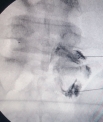

Eski Lomber Stabilizasyon Sistemi Altında Kırık (2)